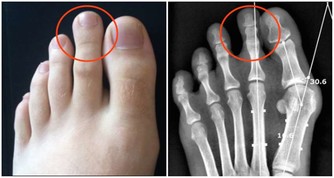

公孫穴屬足脾經經脈的穴道,位於人體足內側緣,在腳中拇趾後大約2寸左右的地方(見下圖),沿著腳拇指後的腳掌骨按壓,什麼時候有酸脹或是酸痛的感覺就證明找對地方了。與脾胃有關的問題,都有很好的調治效果。

▲公孫穴

公孫穴可以抑制胃酸,如果出現吐酸水,趕緊揉一下公孫穴,很快就會好轉。公孫穴可增加小腸蠕動,增強消化能力,吃完東西不消化也要趕緊揉揉它,很快就會往下運化了。公孫穴是我們身上自帶的“健脾胃良藥”,是調理脾胃的保健師。